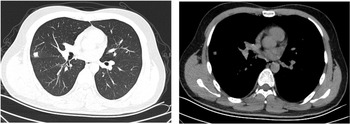

The patient was a 16-year-old male. He started to have fever 7 days prior to visiting our clinic. His maximum temperature was 39.9 °C. He also presented with a cough and white phlegm. The patient visited our emergency department on the second day of disease onset. The lung CT scans revealed ‘right middle lobe medial segment inflammation and consolidation’. The results of a routine blood test were: leukocyte count 5.3 × 109/l, neutrophil count percentage 78.6%, neutrophil count 4.17 × 109/l, lymphocyte count 0.65 × 109/l, CRP 21.28 mg/l. The patient's condition did not improve after self-administration of arbidol and cefdinir. The patient was subsequently treated with ceftazidime and an intravenous infusion of azithromycin, but his condition was still not alleviated. A routine follow-up blood test 7 days after disease onset revealed the following: leukocyte count 9.8 × 109/l, neutrophil count percentage 87.6%, neutrophil count 8.54 × 109/l, lymphocyte count 0.86 × 109/l, CRP 82.80 mg/l. The lung CT scans (Fig. 2) showed right middle lobe inflammation and expanded areas of consolidation, new signs of inflammation in multiple lobes bilaterally and bilateral (mainly right-sided) pleural effusion. The patient was admitted to the ward for further treatment.

Fig. 2. Chest CT of case 2.